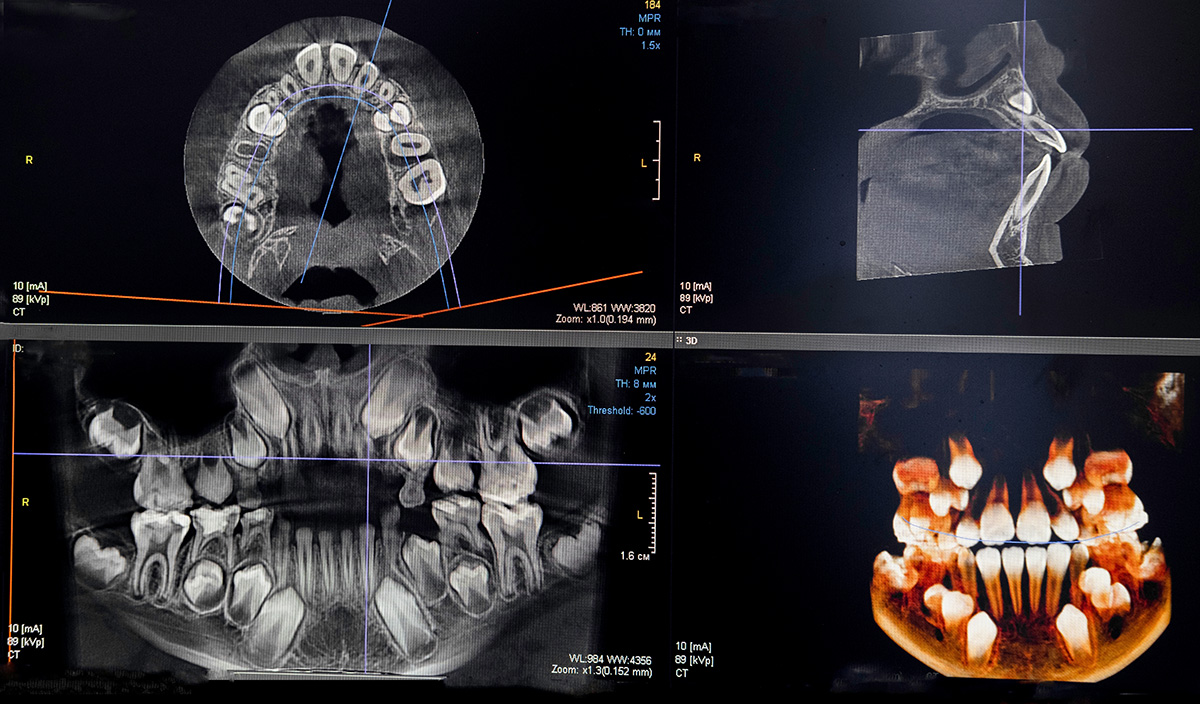

X-Rays & 3D Cone Beam CT

Dental X-rays and 3D imaging allow us to detect hidden issues and provide accurate, effective treatment. Our state-of-the-art technology ensures a safe, detailed view of your teeth, gums, and jaw for better diagnosis and care.

- Comprehensive View: 3D imaging provides a full scan of your teeth, nerves, and jaw for precise treatment planning.